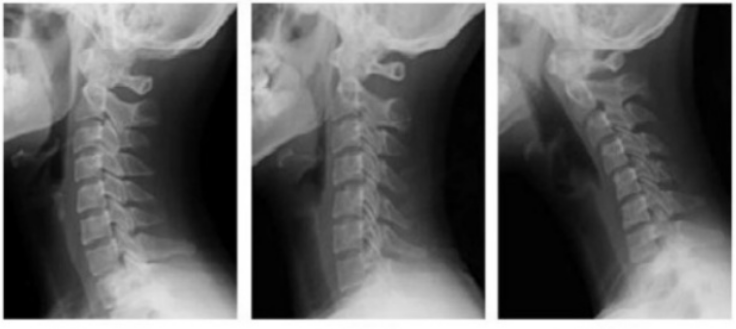

거북목 증후군이라는 증상이 말 그대로 목을 내밀고 있는 증상인데, Xray를 통해서도 쉽게 확인이 가능하다.

아래 X ray 결과 왼쪽이 정상 사람의 X ray 결과이다. 약간 뒤쪽으로 뼈가 휘어서 활처럼 모습을 보이고 있다.

이게 정상이다.

거북목이 되기전 일자목의 상태를 거치는데 가운데 x ray 그림의 결과가 일자목이다.

거북목 초기증상으로 볼 수 있을정도로, 관리가 필요한 상태이다.